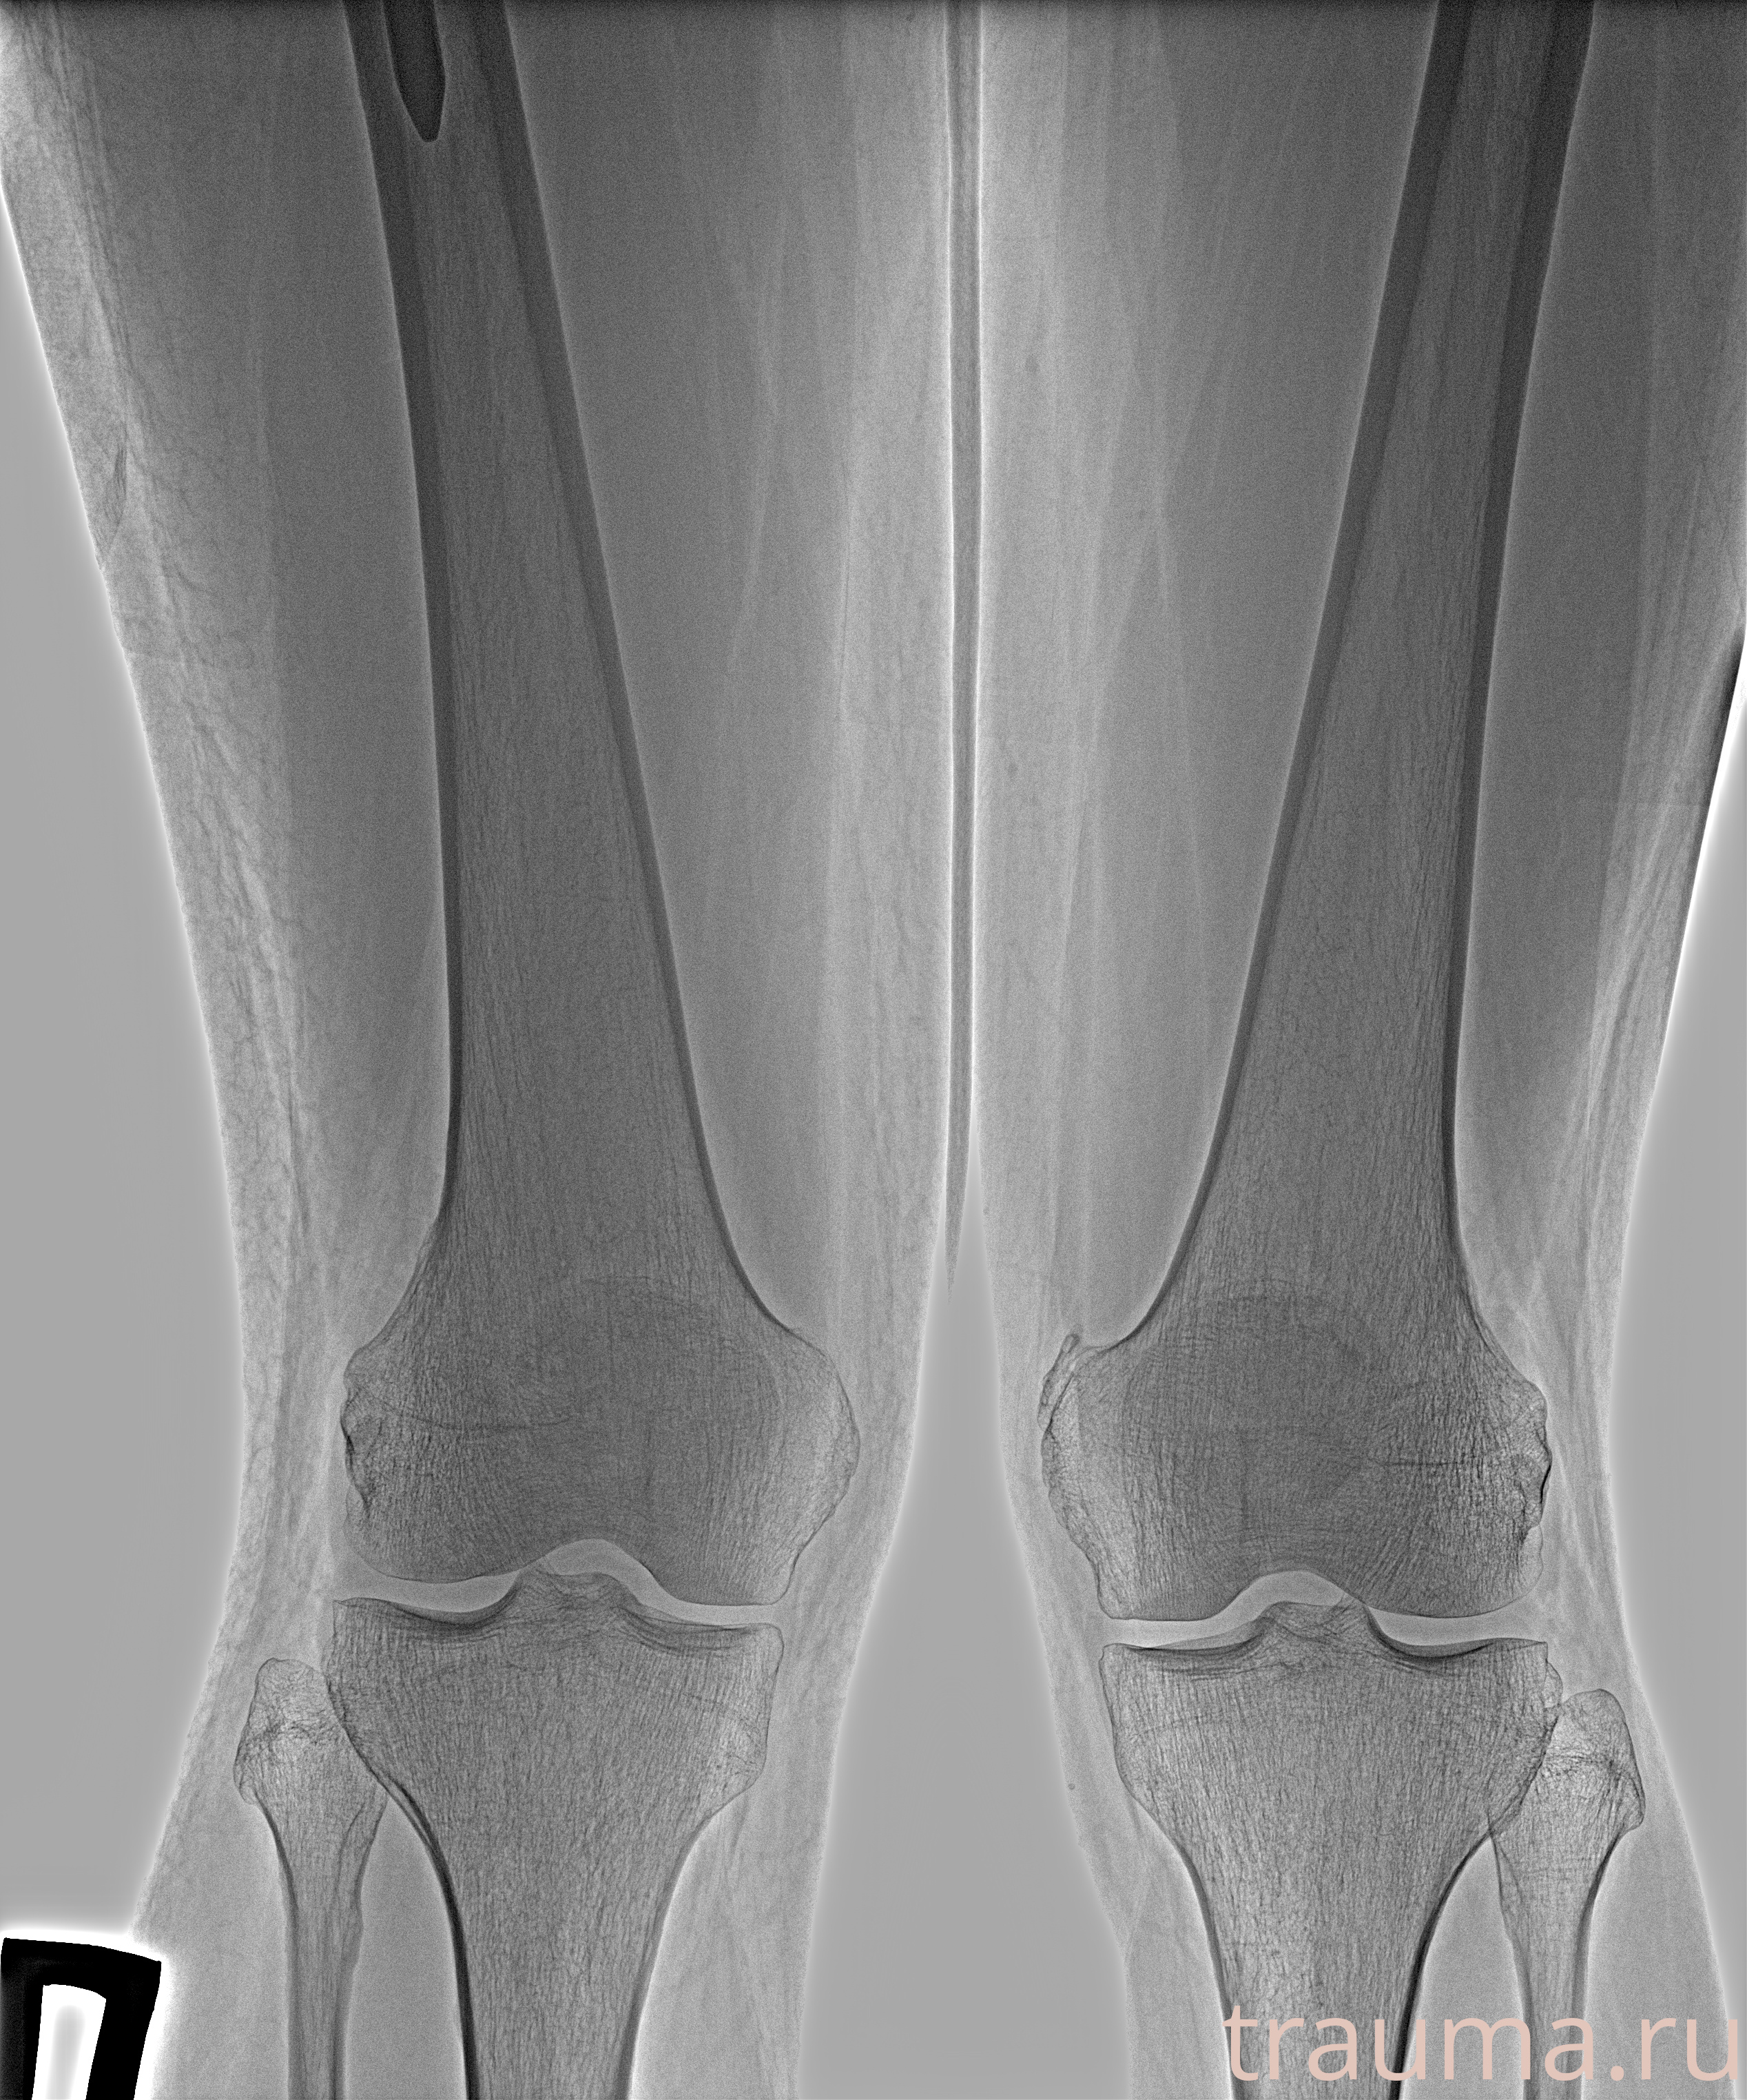

Рентген на дому: по вашему адресу приезжает врач-рентгенолог, травматолог-ортопед с мобильным рентгеновским аппаратом, проводит диагностику травмы или заболевания, делает необходимые рентгенограммы, дает рекомендации по дальнейшему лечению. Получить качественные снимки в домашних условиях возможно благодаря уникальной методике, разработанной МосРентген Центром для института  Склифосовского